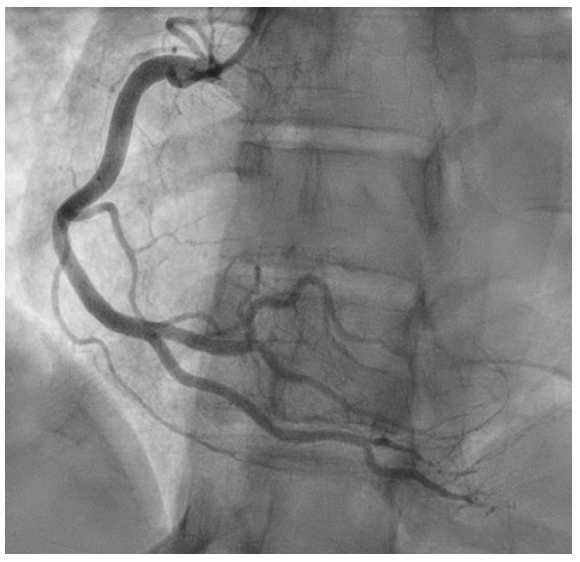

病史摘要:48岁男性患者,2025年10月24日9:40工作时突发意识丧失、小便失禁、呕吐。3年前曾行PCI术,高血压、糖尿病用药不详。 诊疗过程:入院查体神情萎靡、神志模糊等,血压低。心电图提示STEMI,实验室检查多项指标异常。西医诊断为急性前壁高侧壁心肌梗死合并心源性休克(Killip IV级)等,中医诊断为卒心痛(气虚血瘀证)。11:08行冠状动脉造影,对前降支病变处理,术中患

起博心律患者出现胸痛应紧急再灌注?你如何判读

病史摘要:74岁男性,有非缺血性心肌病病史及双心室起搏器植入史。因间歇性胸痛2天,持续4小时,伴大汗、呼吸短促至急诊科就诊。诊疗过程:患者生命体征正常,12导联心电图显示心房感知双室起搏伴室性早搏,符合起搏心律下的Aslanger模式,提示下壁闭塞性心肌梗死。两小时后出现多形性室性心动过速。首次高敏肌钙蛋白I显著升高,被诊断为非STEMI,入院至置管时间20小时。血管造影显示右冠状